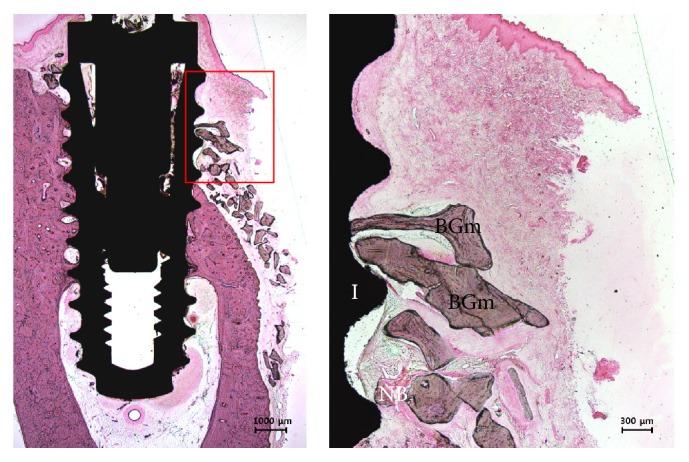

The purpose of this study is to evaluate the effect of three-dimensional preformed titanium membrane (3D-PFTM) to enhance mechanical properties and ability of bone regeneration on the peri-implant bone defect. 3D-PFTMs by new mechanically compressive molding technology and manually shaped- (MS-) PFTMs by hand manipulation were applied in artificial peri-implant bone defect model for static compressive load test and cyclic fatigue load test. In 12 implants installed in the mandibular of three beagle dogs, six 3D-PFTMs, and six collagen membranes (CM) randomly were applied to 2.5 mm peri-implant buccal bone defect with particulate bone graft materials for guided bone regeneration (GBR). The 3D-PFTM group showed about 7.4 times higher mechanical stiffness and 5 times higher fatigue resistance than the MS-PFTM group. The levels of the new bone area (NBA, %), the bone-to-implant contact (BIC, %), distance from the new bone to the old bone (NB-OB, %), and distance from the osseointegration to the old bone (OI-OB, %) were significantly higher in the 3D-PFTM group than the CM group ( < .001). It was verified that the 3D-PFTM increased mechanical properties which were effective in supporting the space maintenance ability and stabilizing the particulate bone grafts, which led to highly efficient bone regeneration.

本研究旨在评估三维预制钛膜(3D-PFTM)对增强机械性能和促进种植体周围骨再生能力的作用。通过新型机械压缩成型技术制作的 3D-PFTM 和手动成型的(MS)-PFTM 通过手工操作,应用于人工种植体周围骨缺损的静态压缩负荷试验和循环疲劳负荷试验。在三只比格犬下颌骨中安装的 12 个种植体中,将 6 个 3D-PFTM 和 6 个胶原膜(CM)随机应用于 2.5mm 种植体颊侧骨缺损,并用颗粒状骨移植材料进行引导骨再生(GBR)。3D-PFTM 组的机械刚度比 MS-PFTM 组高约 7.4 倍,疲劳阻力高 5 倍。3D-PFTM 组的新骨面积(NBA,%)、骨与种植体接触率(BIC,%)、新骨与旧骨之间的距离(NB-OB,%)和骨整合与旧骨之间的距离(OI-OB,%)水平明显高于 CM 组(<0.001)。证实 3D-PFTM 提高了机械性能,这对于支持空间维持能力和稳定颗粒状骨移植物是有效的,从而导致了高效的骨再生。